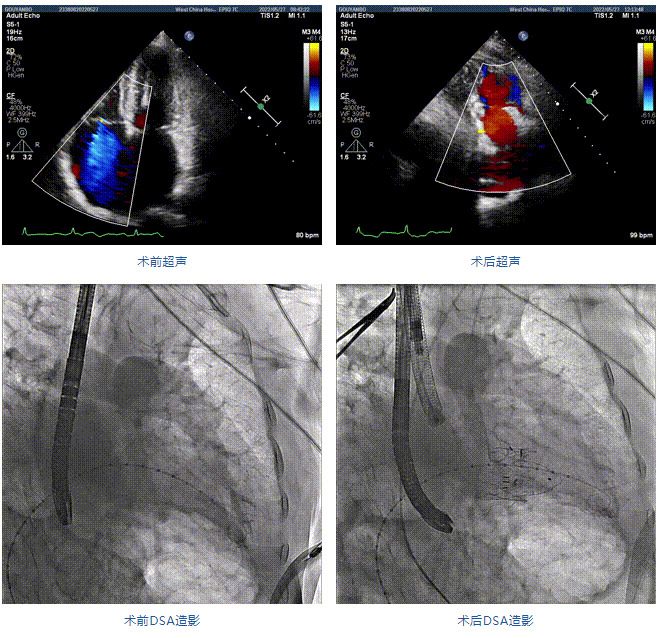

89歲男性。術前超聲報告顯示:雙房增大,左室壁肥厚,主、肺動脈增寬,三尖瓣重度反流。

團隊前期經過多次討論,制定了周密的手術策略和預案。由于患者已是近九旬的超高齡老人,傳統外科開胸手術風險極高,純介入經血管三尖瓣替換能夠明顯減少創傷。術中陳茂及馮沅教授結合體表定位在造影指示下精準穿刺右側頸靜脈并預置兩把血管縫合器。成功建立經皮血管入路后在食道超聲和DSA的引導下順利完成人工瓣膜植入,術后超聲和造影顯示人工三尖瓣同軸性良好,瓣架固定牢靠,無反流和瓣周漏,平均跨瓣壓差降為1mmHg。術畢收緊預置的血管縫合器縫線完成止血,縫合效果滿意,在手術室即刻拔除氣管插管。